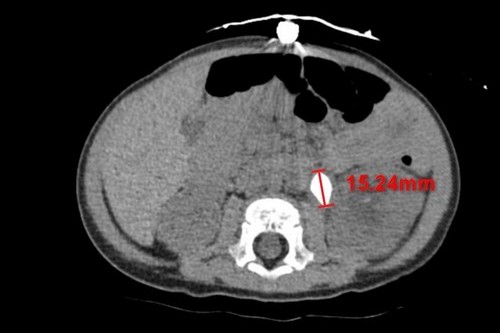

圖說:電腦斷層不同切面顯示,余小弟體內有兩顆約1.5公分大的結石。

二零二二年七月二十五日,花蓮慈濟醫院完成院史上個案年紀最小的腎結石取出手術!年僅十一個月大的男嬰體內長出兩顆約1.5公分的腎結石並造成急性腎臟發炎,小兒腎臟科主任陳明群醫師指出,查找文獻資料也極少在年紀這麼小的孩子身上發現長有這麼大顆的腎結石的紀錄,這種情況相當罕見,因而如何將石頭順利拿出並取乾淨,對醫療團隊也是個挑戰。

今年七月初,出生僅十一個月的余小弟因發燒就醫,原先以為只是單純的泌尿道感染,沒想到照了腎臟超音波,發現腎臟裡有兩顆超過一公分的結石,其中一顆堵在輸尿管與腎臟的銜接處,造成堵塞與腎水腫。余小弟的媽媽表示,早在今年三、四月的時候孩子就曾因泌尿道感染而發燒,到其他醫院治療,當時透過藥物控制下來,燒退後就回家了,沒想到這次又再發生。